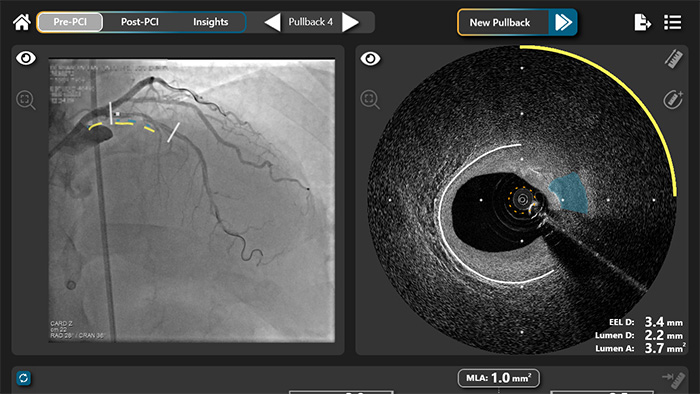

El sistema de imagen HyperVue de SpectraWAVE es una plataforma de imagen intravascular que combina DeepOCT (tomografía de coherencia óptica de nueva generación y alta capacidad) y NIRS (espectroscopia de infrarrojo cercano) dentro del nuevo segmento de imagen Enhanced Vascular Imaging (EVI), proporcionando imágenes estructurales y composicionales detalladas de las arterias coronarias durante las intervenciones coronarias percutáneas. El sistema permite una configuración y adquisición rápidas, así como un análisis automatizado de imágenes mediante inteligencia artificial. En combinación con Eagle Eye Platinum digital IVUS y las tecnologías IntraSight de Philips, HyperVue ampliará el abanico de herramientas de imagen intravascular disponibles para los clínicos —IVUS, DeepOCT, NIRS y fisiología usando la guía de presión y de angiografía— todas ellas combinadas a través de sistemas integrados para adaptar la guía a cada paciente y lesión.